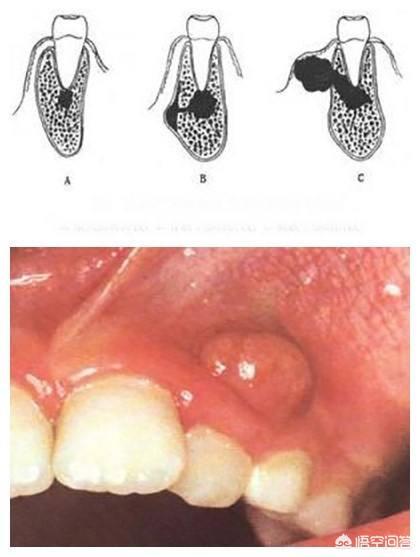

1. inflammation périapicale

Lorsque la dent est cariée ou traumatisée, les bactéries envahissent le tissu pulpaire et l'infection se propage aux tissus périapicaux et se transforme en inflammation périapicale, la dent se détache, avec une sensation de flottement et une douleur lors de la mastication.

1. traitement de l'inflammation périapicale

Le meilleur traitement des infections périapicales est le traitement de canal. Le médecin utilise des instruments spéciaux pour éliminer l'infection du canal radiculaire et scelle ensuite le canal à l'aide d'un matériau biocompatible afin d'empêcher l'infection de pénétrer à nouveau. Une fois l'inflammation périapicale résorbée, la dent ne se détachera pas et ne donnera pas l'impression de flotter.

3. maladie périapicale .En cas d'inflammation dans la zone périapicale de la dent affectée, en particulier en cas d'inflammation aiguë, la dent affectée présente une sensation de flottement et de déchaussement.

Programme de traitementDrainage ouvert + anti-inflammatoire pour soulager les symptômes inflammatoires aigus. Après la disparition de l'inflammation aiguë, en fonction de l'état de la dent, des lésions périapicales, il convient de décider s'il faut procéder à un traitement du canal radiculaire pour conserver la dent affectée, ou à l'extraction de la dent.

4. les lésions telles que les tumeurs kystiques des mâchoires.Lorsque des kystes, des tumeurs ou d'autres lésions dans l'os de la mâchoire qui renferme les dents altèrent considérablement la qualité de l'os de la mâchoire, les dents situées dans la zone de la lésion se déchaussent.

Options thérapeutiques : traitement chirurgical des lésions de la mâchoire, extraction des dents dans la zone focale ou chirurgie apicale.